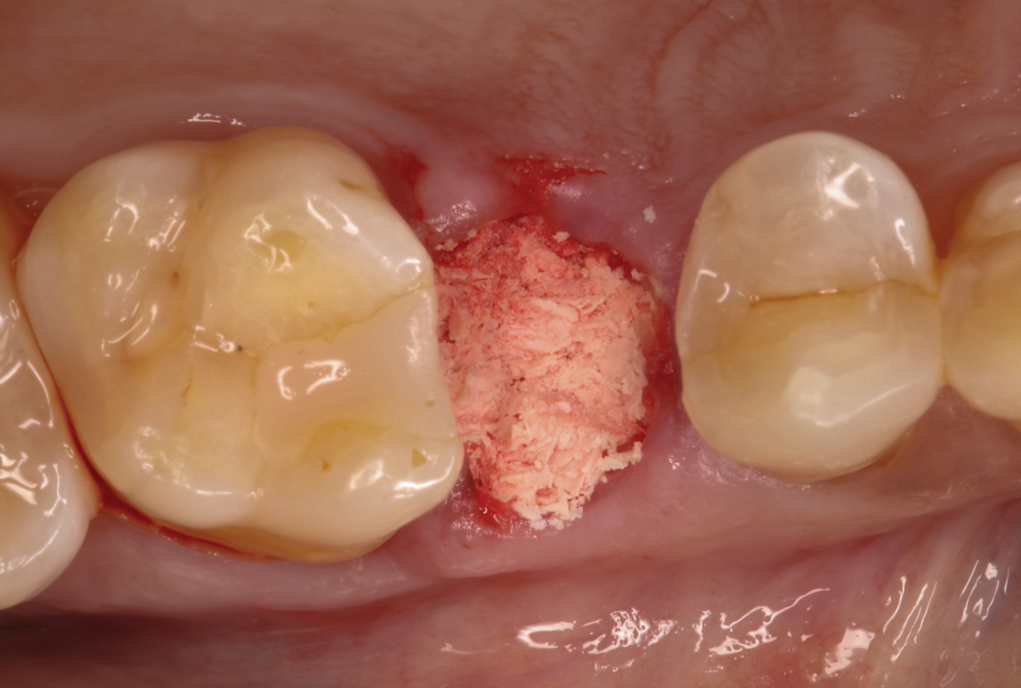

The absorbable bone scaffold material (Figure 3) was quickly hydrated in a sterile saline solution and adapted into the extraction socket with cotton pliers. The material was placed to the level of the adjacent soft-tissue margin, and any excess was removed (Figure 4). Light pressure with a dampened gauze was applied for 1 minute, allowing blood clot formation around the bone scaffold. Fast-setting cyanoacrylate adhesive dressing was used to seal the coronal aspect of the absorbable bone scaffold (Figure 5).

Fig 4. Absorbable bone scaffold material was adapted into the extraction socket and placed level with the soft-tissue height without condensation.

Figure 4